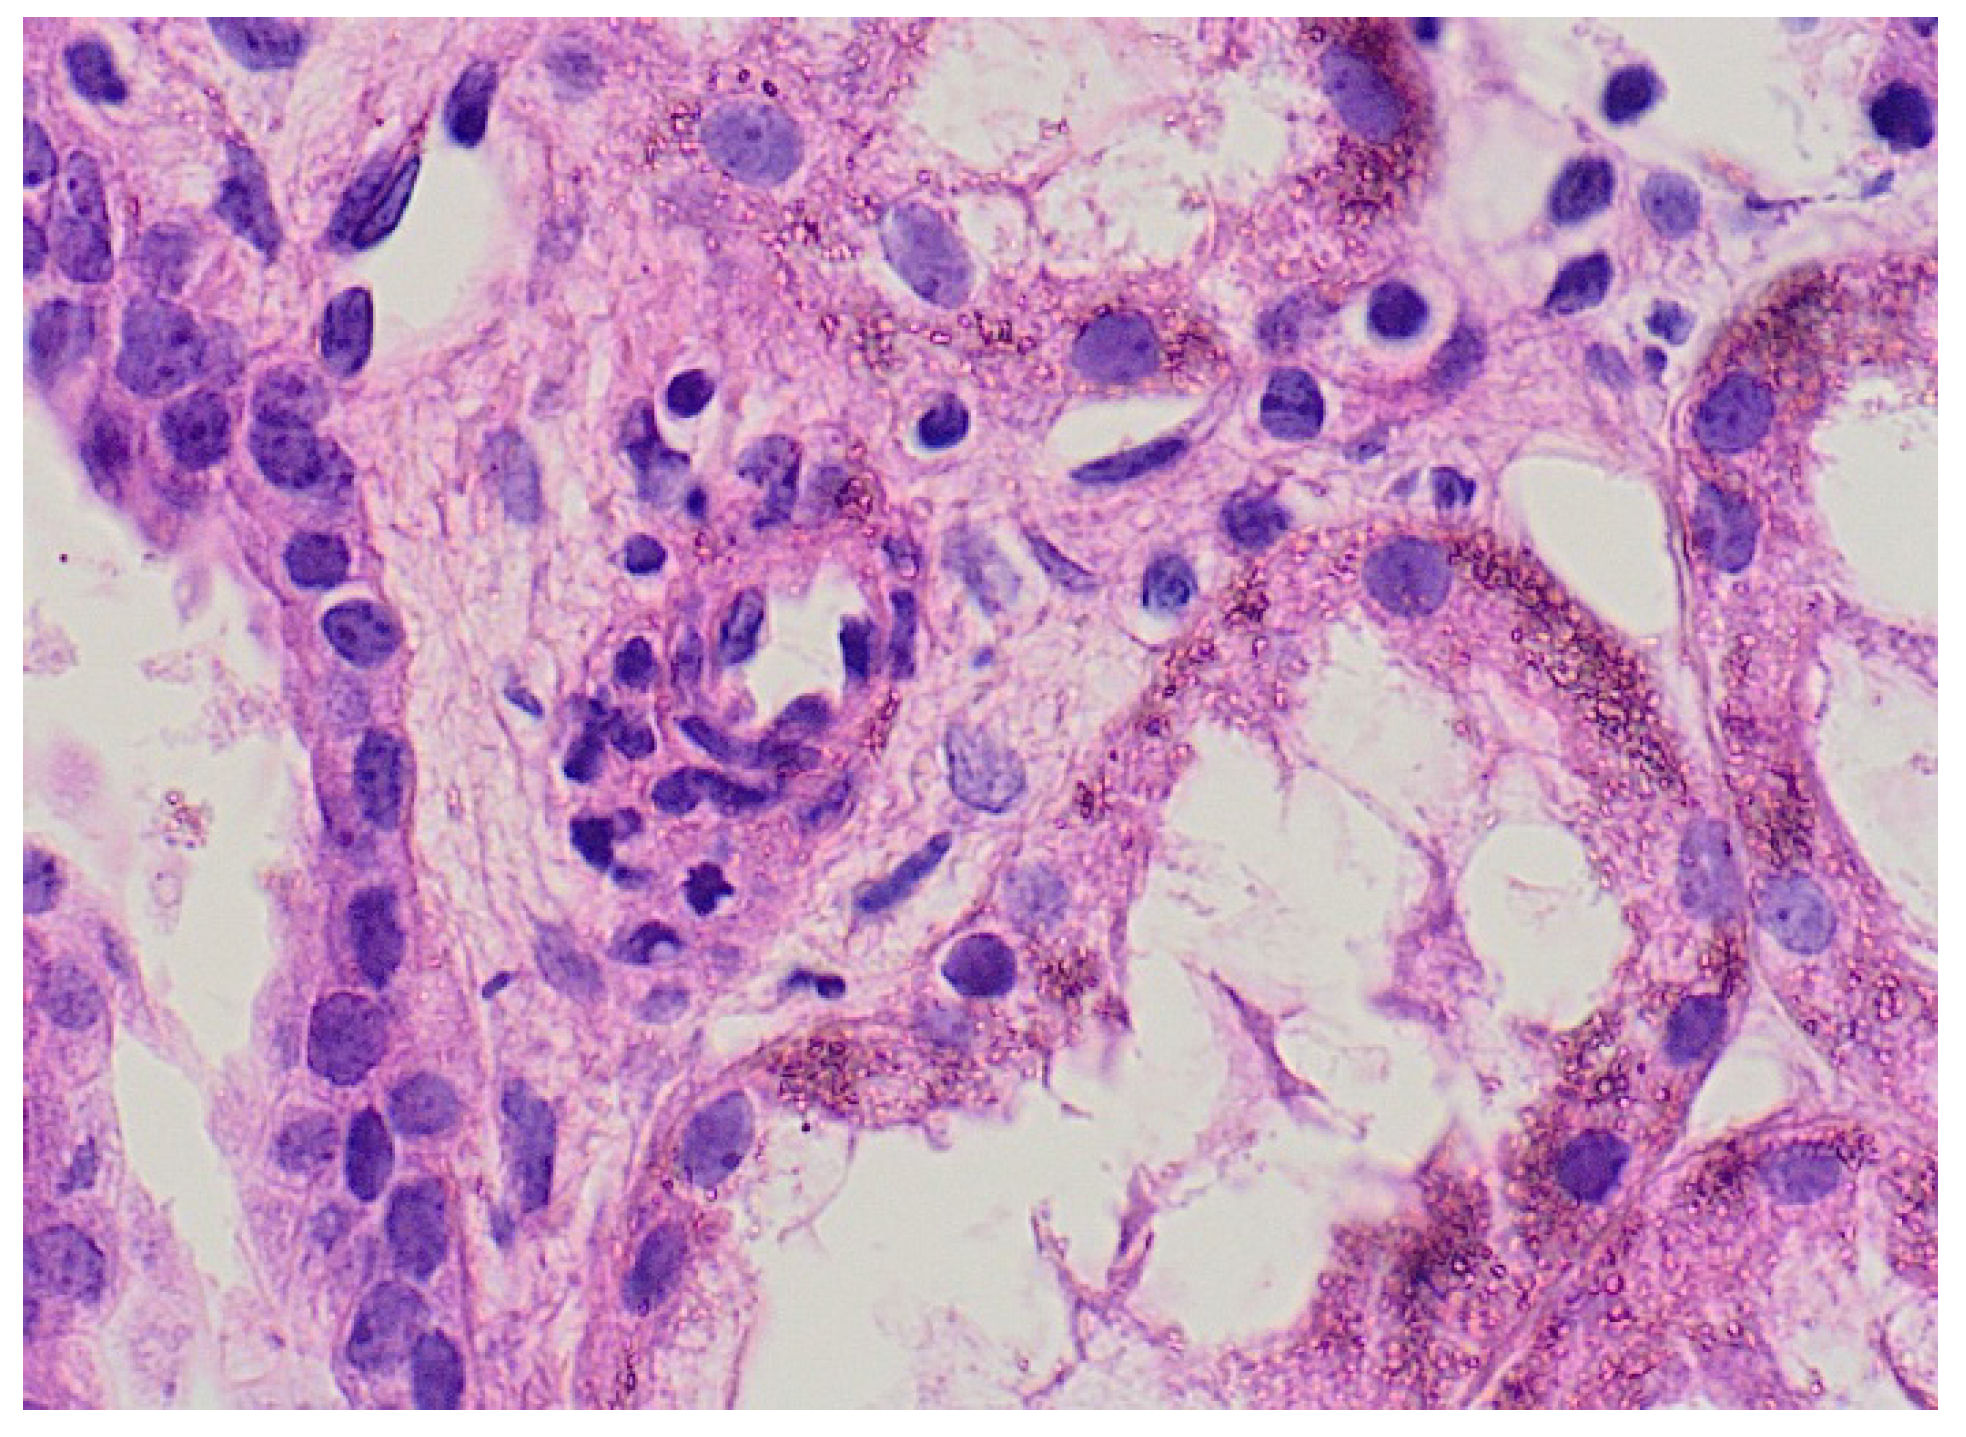

The characteristic rash was the most common presentation; it was present in 100% of cases, was primarily distributed over the legs with some inclusion of the buttocks and upper extremities and had a mean duration of 5.25 ± 0.9 days. The rash was bullous and hemorrhagic in two cases, with an excellent response to pulse steroid treatment. Skin biopsy was performed in two patients with findings of leukocytoclastic vasculitis with IgA deposition (Figure 3).

Figure 3.

Skin biopsy from 3-year-old boy with picture of leukocytoclastic vasculitis.